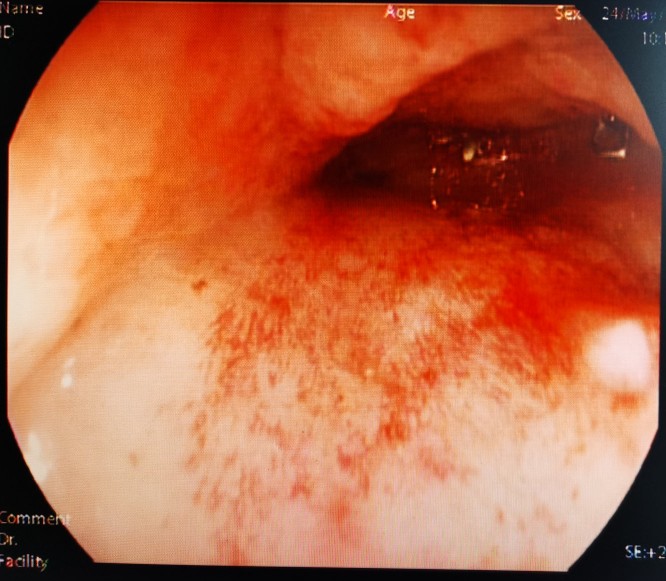

经造瘘口肠镜向下观察